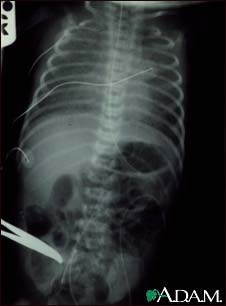

Totally anomalous pulmonary venous return (TAPVR) is a form of congenital heart disease.